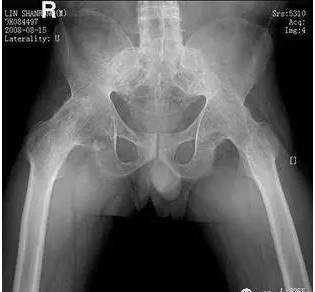

男,32岁,因强直性脊柱炎18年,驼背畸形,左髋关节活动明显受限,右髋关节无功能,髋关节X光正位片显示:左髋关节间隙变窄,关节边缘增生,股骨头表面粗糙,右髋关节3/4骨性融合。

诊断:强直性脊柱炎左髋关节骨性强直